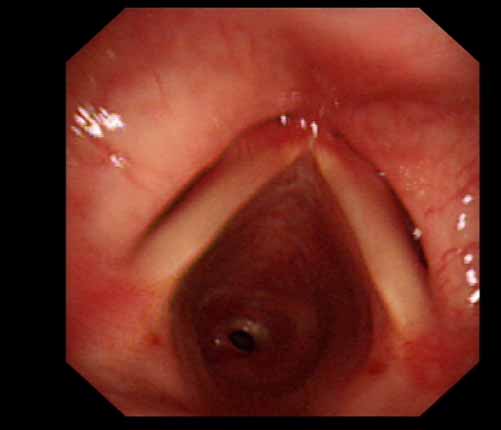

患者李某某,女,45歲,因氣管插管咳嗽、喘憋10天入院。頸部CT檢查示聲門下約20mm處氣管明顯狹窄,狹窄段長(zhǎng)約26mm,最窄處直徑約4.4mm。支氣管鏡檢查見(jiàn)聲門下約2cm氣管呈漏斗狀縮窄,直徑約4-5mm,支氣管鏡無(wú)法通過(guò)。經(jīng)科室討論,決定行電子支氣管鏡下氣管球囊擴(kuò)張治療。與患者及家屬充分溝通并經(jīng)三方見(jiàn)證談話簽署知情同意書(shū)后,在患者持續(xù)吸氧、局麻下,科主任于世倫主任醫(yī)師帶領(lǐng)治療小組為患者實(shí)行電子支氣管鏡下氣管球囊擴(kuò)張術(shù)。手術(shù)過(guò)程順利,出血量很少,術(shù)后患者呼吸困難癥狀即可明顯緩解。10天后行二次擴(kuò)張,患者日常活動(dòng)無(wú)明顯喘憋,二次術(shù)后5天出院。

術(shù)前聲門下的漏斗樣狹窄口